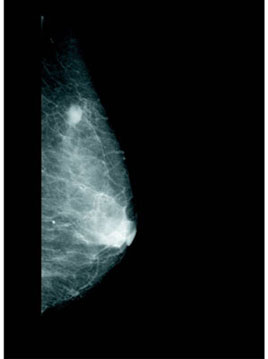

fig6 乳房X線写真(マンモグラフィ)

いろいろなX撮影の中で、乳房撮影が特に注目される理由は、その画像内に描写される疾患(ガン)が非常に小さいことと、その形が重要であることによります。

写真を読影する医師は(fig6)写真上の白い塊の陰影に加え、数100ミクロンに及ぶ小さな白点(微少石灰化)を探すとともに、その形に注目します。特にこの微少石灰化は乳ガンの入り口にあたるため(初期乳ガン)、特に重要と言われています。